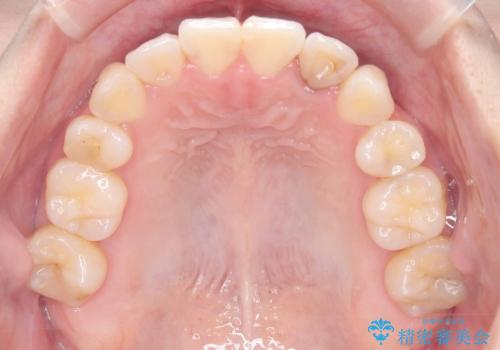

- 「歯のでこぼこを治したい」を主訴に来院された患者様です。 上下ともに、歯のでこぼこが強く、上下左右4の抜歯をし、ワイヤー矯正で治療を行いました。

かなり綺麗に並ぶ事ができ大変満足していただけました。

叢生量がかなり多かったのですが、歯肉退縮も失活歯も無くとても綺麗な歯並びになりました。